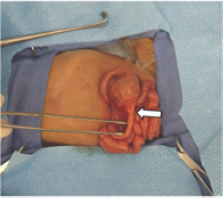

Figure 3: Surgical pathology. The proximal jejunum is markedly dilated with focal area of narrowing, consistent with the site of atresia, which was approximately 5 cm distal to the ligament of Treitz.

The infant was admitted to the neonatal intensive care unit, and surgery was performed the next day. A transverse incision was made in the right upper quadrant. The small bowel was eviscerated and closely inspected from ligament of Treitz to rectum. Proximal jejunum was moderately dilated. There was an abrupt diameter change at the area of atresia, which was approximately five cm distal to the ligament of Treitz (Figure 3). After division of the mesentery, a segment measuring three cm of jejunum proximal to the atresia and one cm distal to the atresia was resected. Injection of saline into the distal bowel confirmed patency of the remaining small and large bowel loops. A single layer anastomosis was created with absorbable suture in an interrupted fashion. The mesentery defect was also closed to prevent internal hernia.